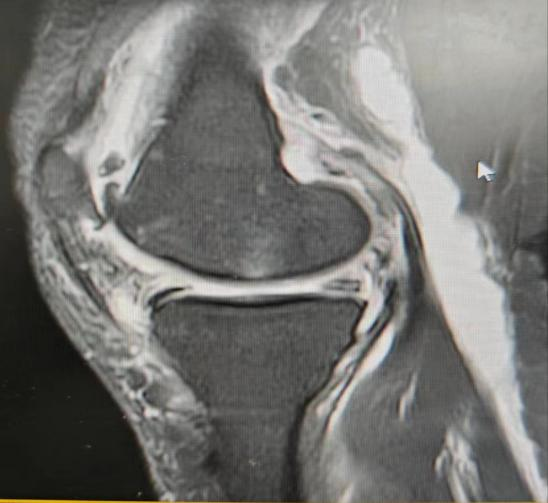

病例1,患者左膝关节疼痛不适半年,行经查体及MRI检查诊断为:左膝内侧半月板损伤、腘窝囊肿、骨性关节炎,给予行“左膝关节镜下内侧半月板、软骨修整成形及腘窝囊肿切除术”。

病例2,患者左膝关节疼痛不适2月,经查体及MRI检查诊断为:左膝内外侧半月板损伤、腘窝囊肿、骨性关节炎,考虑囊肿较小,且为单房囊肿,行“膝关节镜下半月板、软骨修整成形术”的同时,给予切除“活瓣”,行“腘窝囊肿减压术”。

腘窝囊肿又叫“Baker囊肿”,分为原发性和继发性两种,前者儿童多见,后者中老年多见,绝大多数的腘窝囊肿继发于膝关节内病损,包括半月板损伤、骨关节炎、类风湿关节炎、色素沉着绒毛结节性滑膜炎等。发病原理是单向流通的“活瓣”(只进不出),即腘窝囊肿通道口存在的皱襞、束带或关节内疾患堵塞通道口,增多的关节积液可通过通道进入滑囊,但不能从滑囊回到关节腔,导致囊肿的形成和持续存在。目前膝关节镜下腘窝囊肿切除术已成为主流手术方式,关节镜下不仅能切除囊肿,还能处理半月板损伤、骨关节炎等关节内疾病,大大降低了复发的几率。